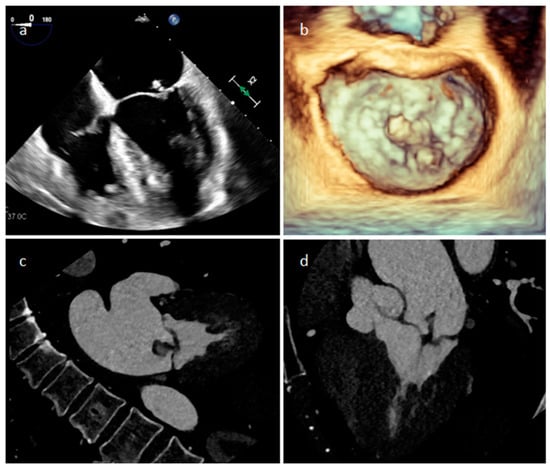

| Myxoma | Adulthood. Carney complex. | LA | Usually, asymptomatic. Rarely, intracardiac obstruction, embolic events and constitutional symptoms | Mobile mass arising from the IAS | Globular or spherical, with a friable surface and heterogeneous internal echogenicity | Heterogeneous, low attenuation, may be calcified | Isointense T1w, High T2w, heterogeneous LGE |

| Papillary fibroelastoma | Adulthood | Valves | Usually, asymptomatic. Rarely embolic events | Atrial side of the mitral valve or the aortic surface of the aortic valve leaflet | Stippling and vibration or shimmer of the peripheral edge. | Hypodense, smooth, peduncolated, attached to the valve leaflet by a short pedicle | Iso T1w, Hyper T2w, hypo cine with surrounding turbolent flow, poor LGE |